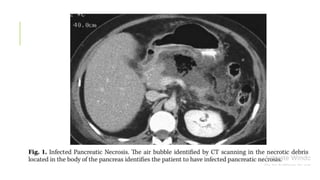

The presence of infection in pancreatic necrosis is confirmed by

either:

(1) radiographic evidence of extra-luminal gas located in the area of

necrosis as seen on cross-sectional imaging